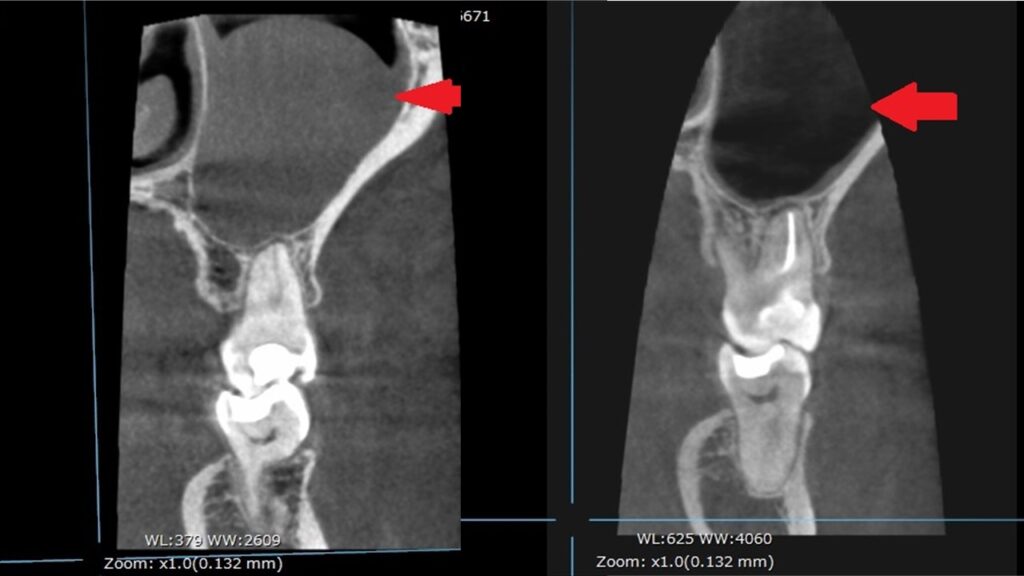

横からの画像。(左:治療前 右:治療後)

正面からの画像です。

膿が無くなりました(^^)/

しっかりと治療することで、症状はなくなり、良い状態で治療を終えることができます。

ほぼ1年後も状態が落ち着いて、治ってくれてよかったですね(*^^*)